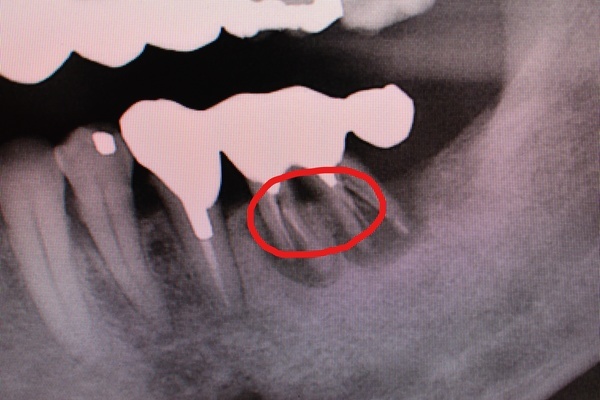

写真は⑤⑥7の延長ブリッジに歯根破折が生じたものです。

延長ブリッジは、歯根破折や歯の動揺が生じやすく、あまりおすすめはできない治療法です。